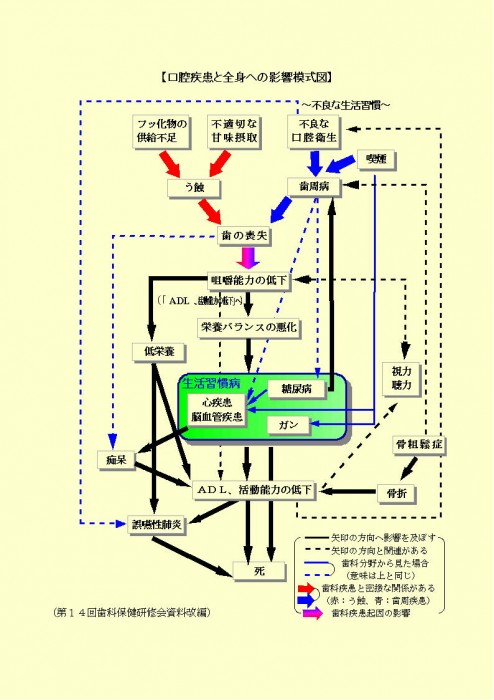

【メリット4】他の全身の病気になる危険性を少なくできる!

その他にも口臭による営業活動への悩みの防止、歯を失うことでかみ合わせが不安定になり腰痛や食事困難で体が弱ったりするなどの全身への影響による仕事への悪影響の防止、福利厚生の充実した企業・事業所というPR効果など幅広いメリットを生み出すことが可能と考えられます。

お口の病気は、全身への病気になるもとです!